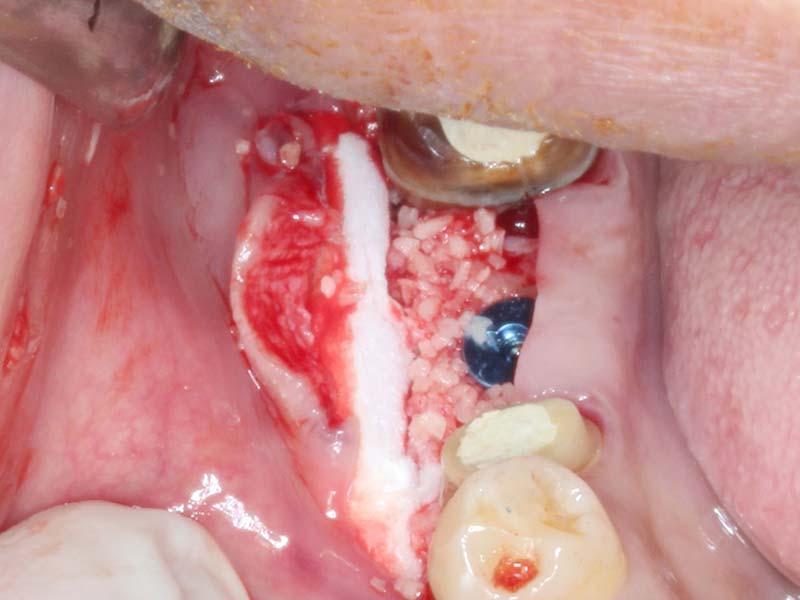

組織增生 首頁 案例分享 組織增生 組織增生 組織增生 缺牙過久,導致組織塌陷 植牙同時合併使用骨粉促進骨頭再生 植牙同時合併使用膠原蛋白,促進牙齦再生 組織穩定後再使用人工皮再增進角化牙齦 Before After 達到理想的組織增生再造